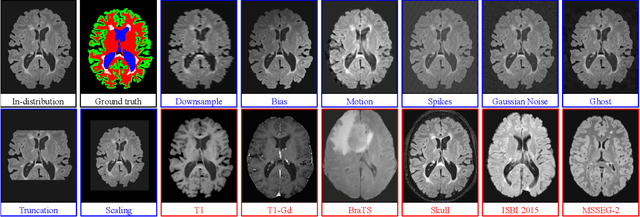

Abstract:Deep Learning models are easily disturbed by variations in the input images that were not seen during training, resulting in unpredictable behaviours. Such Out-of-Distribution (OOD) images represent a significant challenge in the context of medical image analysis, where the range of possible abnormalities is extremely wide, including artifacts, unseen pathologies, or different imaging protocols. In this work, we evaluate various uncertainty frameworks to detect OOD inputs in the context of Multiple Sclerosis lesions segmentation. By implementing a comprehensive evaluation scheme including 14 sources of OOD of various nature and strength, we show that methods relying on the predictive uncertainty of binary segmentation models often fails in detecting outlying inputs. On the contrary, learning to segment anatomical labels alongside lesions highly improves the ability to detect OOD inputs.